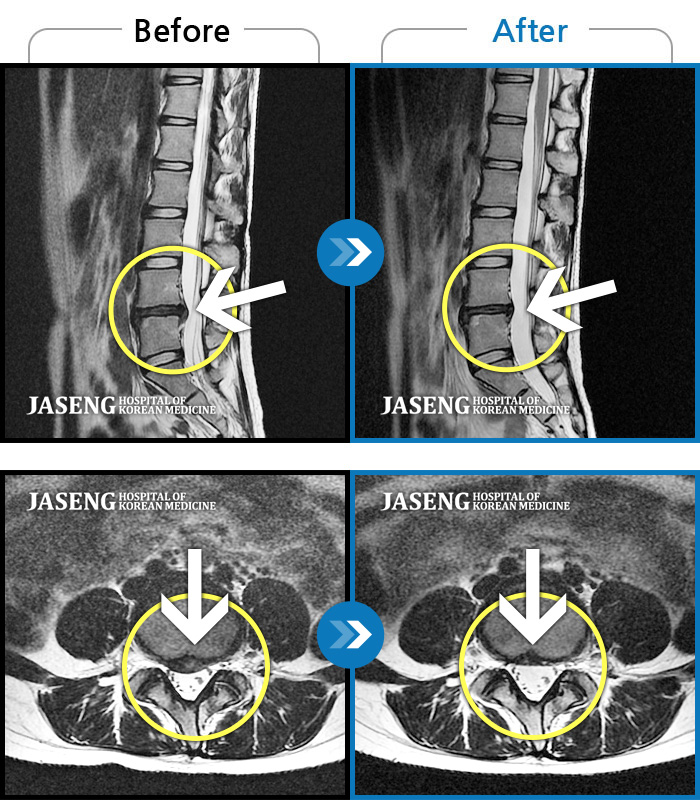

허리디스크

수원 · 김태성 원장

허리 통증과 좌측 대퇴부~종아리 저림과 통증

촬영시기

2011.03.14 ~ 2024.05.24

2024.11.21